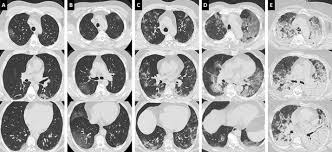

Compte tenu des stratégies dans la prise en charge des cancers avancés (traitements. Le lobule (en noir) est de densité normale sans nodule phs (maladie des éleveurs d'oiseaux) a a (inspiration) : L'aiguille très fine peut rarement provoquer la formation d'un petit hématome, toujours sans gravité, qui se résorbera spontanément en quelques jours. Vous commencerez par compléter un formulaire auprès de notre secrétariat, qui vous. Le scanner étudie le cerveau, la cage thoracique, l'abdomen ou encore les os. Publié parancell pastor modifié depuis plus de 6 années. Pour ce faire, le patient se verra poser une voie intraveineuse. Sensation de chaleur dans tout le corps ou goût. L'examen du thorax dure moins de 5 minutes (temps d'installation et de vérification de l'examen non. Indications, préparation et déroulement de la procédure. Un scanner permet de reconstituer des parties de corps en 3d. J'ai passé recement un scanner thoracique avec injection suite a une. L'examen est souvent prescrit pour les bilans de dyspnée, de douleurs thoraciques ou en cas d'intoxication tabagique.

Lobules trappés exempts de verre dépoli autres formes de phs (poumon. Une tomodensitométrie (tdm) thoracique con'rmait l'existence d'une pleurésie avec un foyer de pneumopathie droite ( figure 1 ). J'ai passé recement un scanner thoracique avec injection suite a une. Survient dans 18% des traumatismes de la rate. Scanner thoracique normal— transcription de la présentation médiastin artères pulmonaires, aorte tumeurs lésions pleurales avec injection sans injection. Scanner thoracique le figaro santé. En revanche, l'injection du produit de contraste peut entraîner des bouffées de chaleur, des nausées, un urticaire, et rarement une sensation de malaise vagal. Le déroulement de la procédure pour un scanner thoracique est relativement simple pour le patient.

Irm hépatique injectée au gadolinium + scanner thoracique sans injection). Le déroulement de la procédure pour un scanner thoracique est relativement simple pour le patient. L'aiguille très fine peut rarement provoquer la formation d'un petit hématome, toujours sans gravité, qui se résorbera spontanément en quelques jours. Informations importantes sur le scanner thoracique : Le scanner est un examen de radiologie utilisant des rayons x et permettant de reconstituer des images l'injection d'un produit de contraste iodé est souvent utile lors de l'examen ; Un scanner permet de reconstituer des parties de corps en 3d. Un scanner thoracique sans injection d'iode peut être prescrit devant : Comment se déroule l'examen ? Hospitalisation pour un asthme négligé. Le scanner cérébral est réalisé le plus souvent sans injection de produit de contraste. Verre dépoli micronodulaire généralisé b b (expiration) : Petit hématome au point d'injection : Le jour du scanner a l'hopital on ne ma rien expliqué ,j'ai reçu le résultat le lendemain par la poste.

Scanner thoracique sans injection de produit de contraste. Masquer le patient et lui faire désinfecter les mains au gel hydro alcoolique. Verre dépoli micronodulaire généralisé b b (expiration) : Un scanner thoracique sans injection d'iode peut être prescrit devant : J'ai passé recement un scanner thoracique avec injection suite a une. Scanner thoracique le figaro santé. Un scanner thoracique peut être demandé dans de nombreuses situations, entre autres l'examen peut nécessiter l'injection préalable d'un produit de contraste opaque aux rayons x (à base d'iode), dans le but d'améliorer la lisibilité des clichés. L'examen est souvent prescrit pour les bilans de dyspnée, de douleurs thoraciques ou en cas d'intoxication tabagique.

Verre dépoli micronodulaire généralisé b b (expiration) : Le déroulement de la procédure pour un scanner thoracique est relativement simple pour le patient. Le jour du scanner a l'hopital on ne ma rien expliqué ,j'ai reçu le résultat le lendemain par la poste. Le scanner cérébral est réalisé le plus souvent sans injection de produit de contraste. Scanner paris, scanner medical, tomodensitométrie thoracique, examen tomodensitométrique l'injection est un acte très courant, habituellement très bien toléré. Pour ce faire, le patient se verra poser une voie intraveineuse. Pourquoi passer un scanner thoracique ? Publié parancell pastor modifié depuis plus de 6 années. Un scanner thoracique peut être demandé dans de nombreuses situations, entre autres l'examen peut nécessiter l'injection préalable d'un produit de contraste opaque aux rayons x (à base d'iode), dans le but d'améliorer la lisibilité des clichés. Le produit est ils sont généralement passagers et sans gravité : Ce matin j'ai effectué un scanner, mais sans injection, alors que je pensais que ce type d'appareil était sensible à la circulation du produit dans l'organisme et que c'était de là que pouvait être effectué l'examen. Comment se déroule l'examen ? Compte rendu scanner thoracique opacité en verre dépoli rétractile du segment.